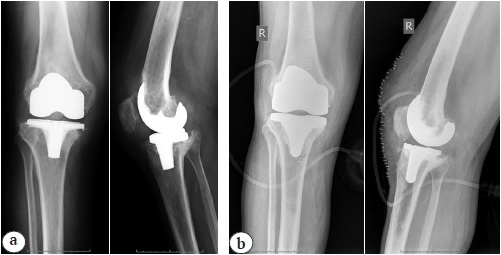

Remodeling of articular surfaces was performed in the group 2 with the use of intramedullary guides and cutting blocks. Stability tests were used to evaluate collateral ligaments tension and flexion/extension of the knee with trial implants in order to determine optimal thickness of officinal liner (Fig. 4).

Fig. 4. X-rays of a 55-year-old patient (2017): a — before surgery; b — after the articular spacer implantation